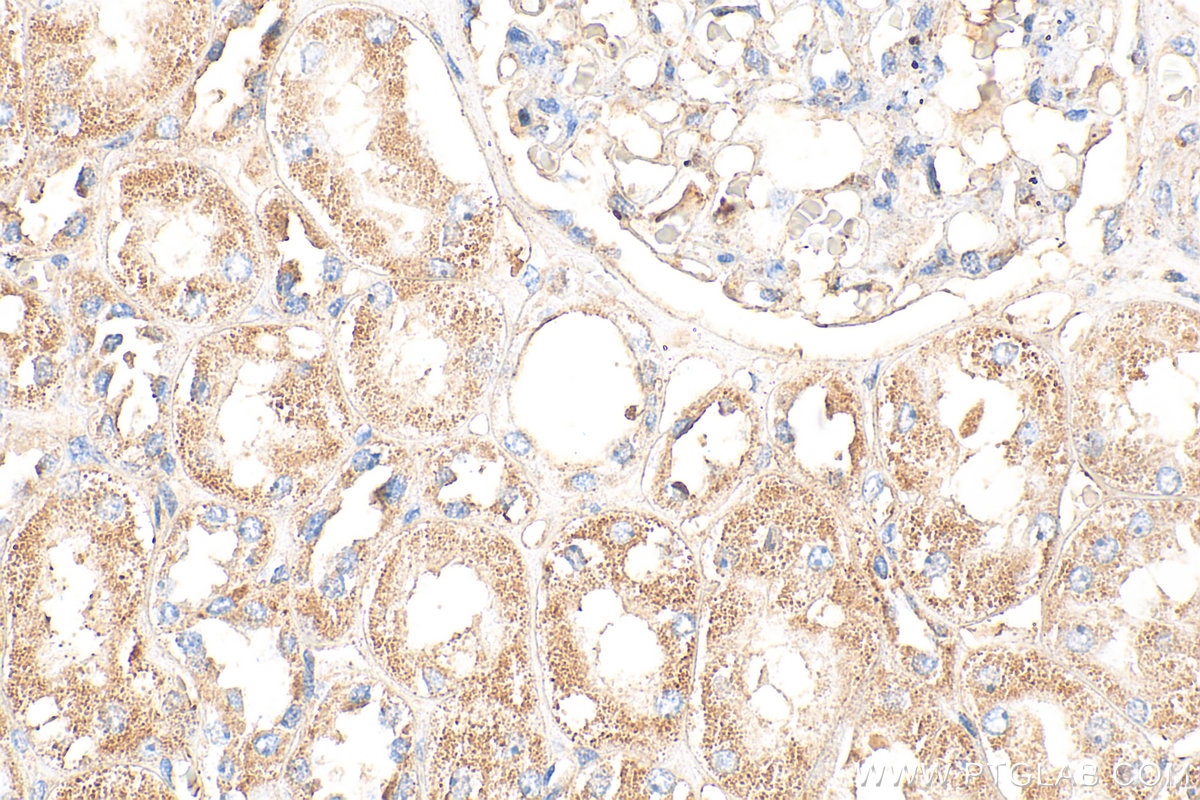

| Positive IHC detected in | human kidney tissue, mouse heart tissue Note: suggested antigen retrieval with TE buffer pH 9.0; (*) Alternatively, antigen retrieval may be performed with citrate buffer pH 6.0 |

20467-1-AP targets Spexin in IHC, IF-P, ELISA applications and shows reactivity with human, mouse samples.

Spexin (SPX), also known as neuropeptide Q, is a novel and highly conserved neuroendocrine peptide discovered through bioinformatics. Spexin and its receptors (primarily galanin receptor types 2 and 3) are widely expressed throughout the body, including the central nervous system, gastrointestinal tract, adipose tissue, kidneys, and cardiovascular system. Research indicates that Spexin is a multifunctional regulatory peptide, with its most central role being in energy homeostasis and metabolic regulation. It functions to suppress appetite, reduce body weight, and improve insulin resistance and glucose metabolism, making it a potential biomarker and therapeutic target for metabolic diseases such as obesity and type 2 diabetes. Additionally, Spexin is involved in regulating various physiological and pathological processes, including pain perception, anxiety- and depression-like behaviors, cardiovascular function, and reproductive activities.